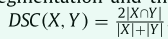

我们在本研究中使用了两个评估指标。 Dice score coefficient (DSC) 使用公式

衡量预测分割和ground truth分割之间的重叠程度,其中 X 和 Y 分别代表预测和ground truth的体素集。 95% Hausdorff Distance(95HD) 是 Hausdorff Distance的变体,它测量 X 中的点到 Y 中最近邻点的最大距离。 HD 计算为两个方向的平均值,HD = (d H (X, Y ) + d H (Y, X)) / 2 。 95% Hausdorff Distance可以通过计算 95% 的最大距离来减轻异常值的敏感性。